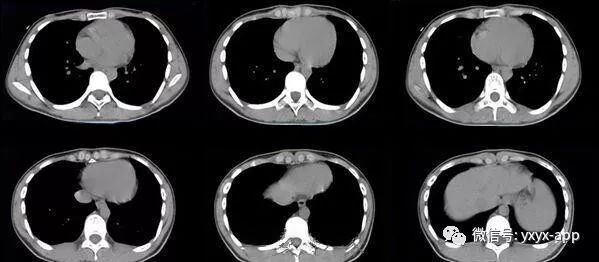

1、两肺较淡的斑片状磨玻璃影,不呈叶段分布,病变可延伸至胸膜下,其中磨玻璃影中可见小结节影,磨玻璃影与正常肺组织分界清楚,形成“地图样”改变,这种地图样分布的原因,可能是由于这种斑片影以肺小叶为病变单位,小叶间隔在一定程度上限制了病变的蔓延;

2、由于小叶间隔和小叶内间隔的增厚形成网格状阴影改变,弥漫的磨玻璃影及其内部的网格小叶间隔增厚形成了“铺路石样”改变;

3、实变区具有多样性,多种不同程度的病变共存,病灶内可见支气管气像;

4、病变部位以肺门及双下肺明显。